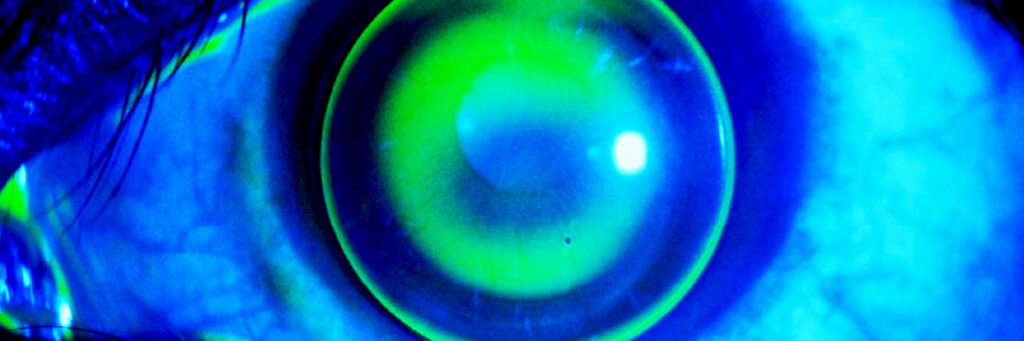

A lente escleral é um tipo especial de lente de contato de grande diâmetro que se apoia na esclera (parte branca do olho) e não diretamente sobre a córnea.

- Forma uma câmara de líquido entre a lente e a córnea, hidratando os olhos e reduzindo desconforto.